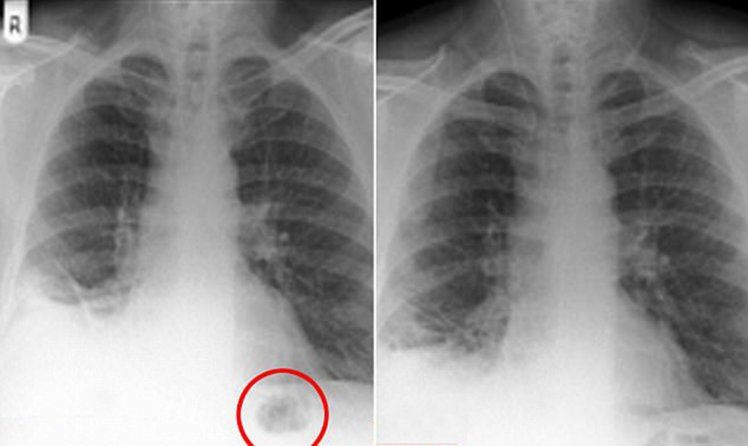

Lelaki berusia 47 tahun dari England kini boleh menarik nafas lega apabila ketumbuhan yang dikesan pada paru-parunya sebenarnya adalah kon trafik mainan.

Selepas mengalami batuk berpanjangan hampir lebih setahun, lelaki berkenaan merujuk pada hospital di Preston, England. Doktor yang melakukan imbasan pada paru-paru pada mulanya menyangka onjek asing itu adalah sejenis ketumbuhan kerana lelaki tersebut adalah seorang perokok tegar.

Memetik laporan The Guardian pula, kon mainan itu merupakan hadiah yang diterima pesakit ketika berusia 7 tahun. Pesakit turut mengakui pernah menelan permainan ketika zaman kanak-kanak, namun tidak menyangka ia terperangkap di paru-parunya.